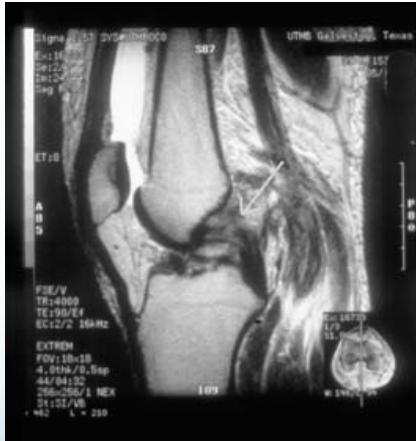

MRI

- Best imaging modality for PCL injuries